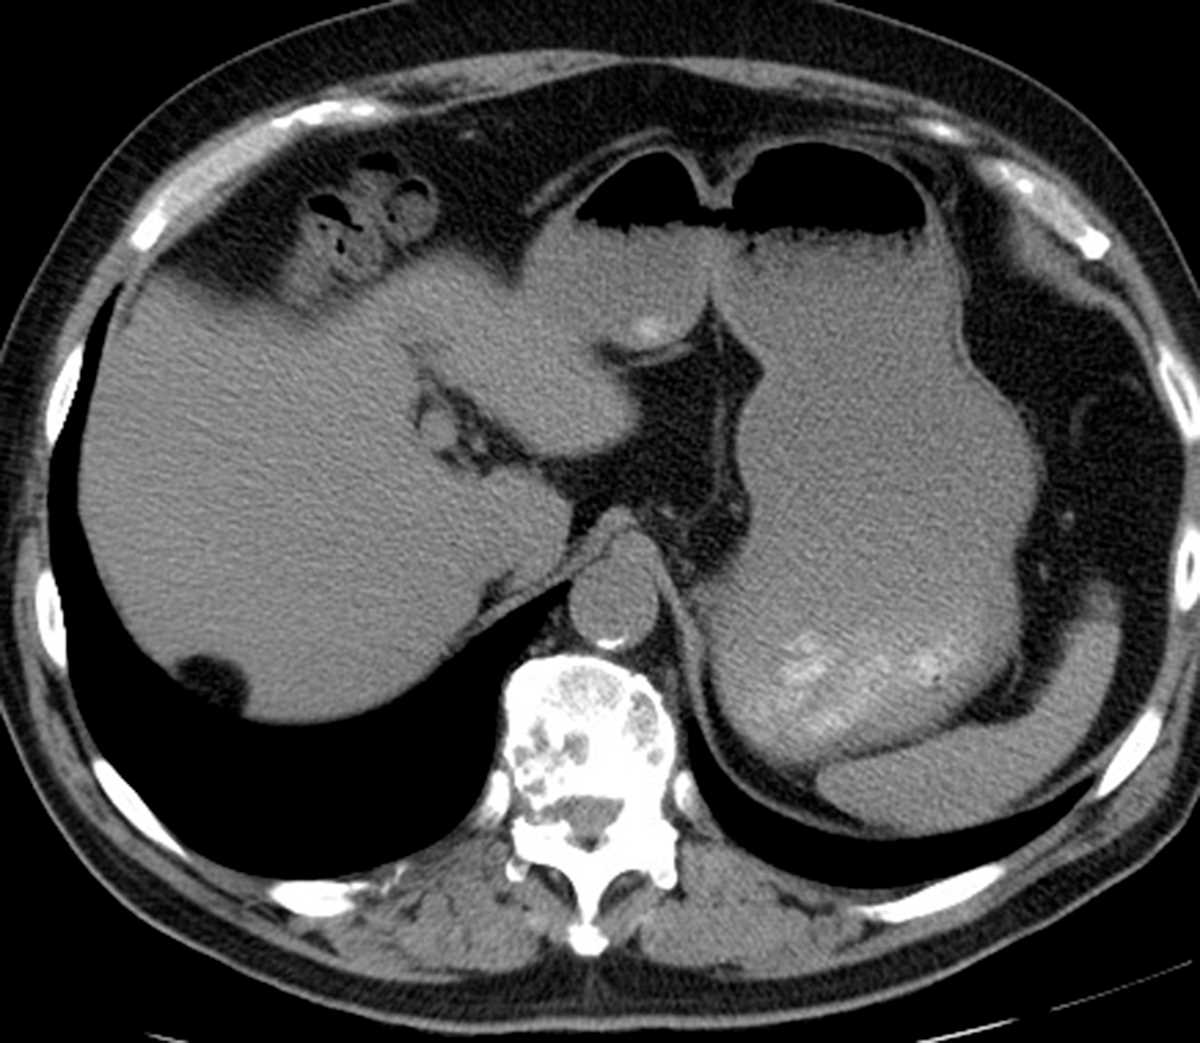

Mucinous Cystic Neoplasm

Multiple MR images demonstrate a T2 bright cystic mass arising from the pancreatic tail. This mass was found to represent a mucinous cystic neoplasm